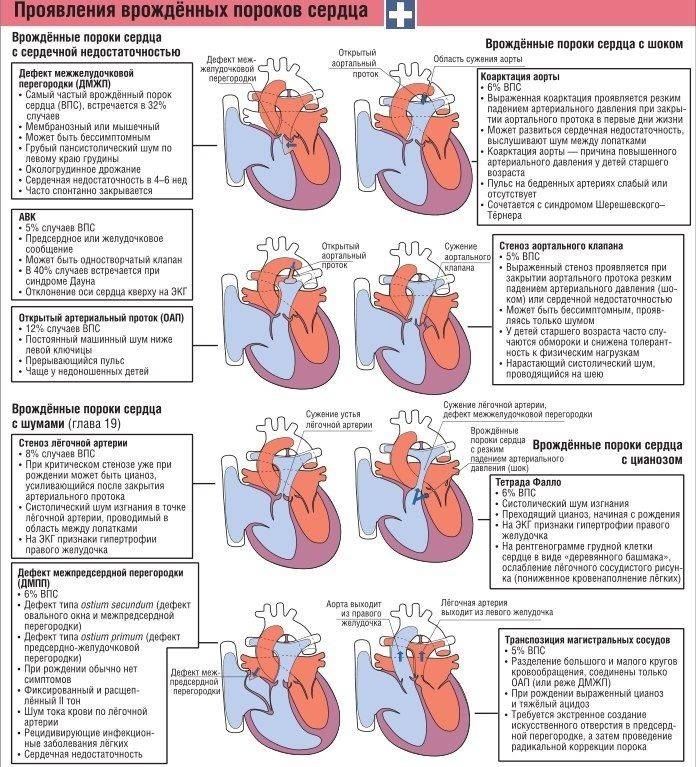

Симптомы ВПС

Уже в первые часы жизни детский организм может сигнализировать об аномалиях развития сердечно-сосудистой системы. Аритмия, учащенное сердцебиение, затруднение дыхания, потеря сознания, слабость, синюшные или бледные кожные покровы свидетельствуют о возможных патологиях сердца.

Но симптомы ВПС могут проявиться и значительно позже. Беспокойство родителей и немедленное обращение за медицинской помощью должны вызвать такие изменения в состоянии здоровья ребенка:

- посинение или нездоровая бледность кожи в области носогубного треугольника, стоп, пальцев, ушей и лица;

- одышка (постоянно затрудненное дыхание или временные приступы);

Типичный симптом синего порока сердца – голубовато-серый, или синюшный, цвет кожи (цианоз кожи)из-за дефицита кислорода в крови. Все синие пороки сердца гемодинамически значимые; цианоз кожи хорошо виден сразу после рождения ребенка.

При отсутствии сочетания АМПП с другими пороками сердца существенные нарушения умственного и физического развития отсутствуют, а клинические симптомы выражены слабо. А вот при сочетании этой патологии с другими пороками могут наблюдаться такие проявления, как:

- акроцианоз (синюшность кожи в носогубном треугольнике);

- одышка (у младенцев может наблюдаться при кормлении грудью);